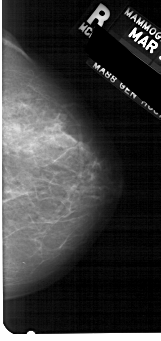

A_1268_1.RIGHT_CC

RIGHT_CC LINES 5101 PIXELS_PER_LINE 2401 BITS_PER_PIXEL 12 RESOLUTION 43.5 NON_OVERLAY